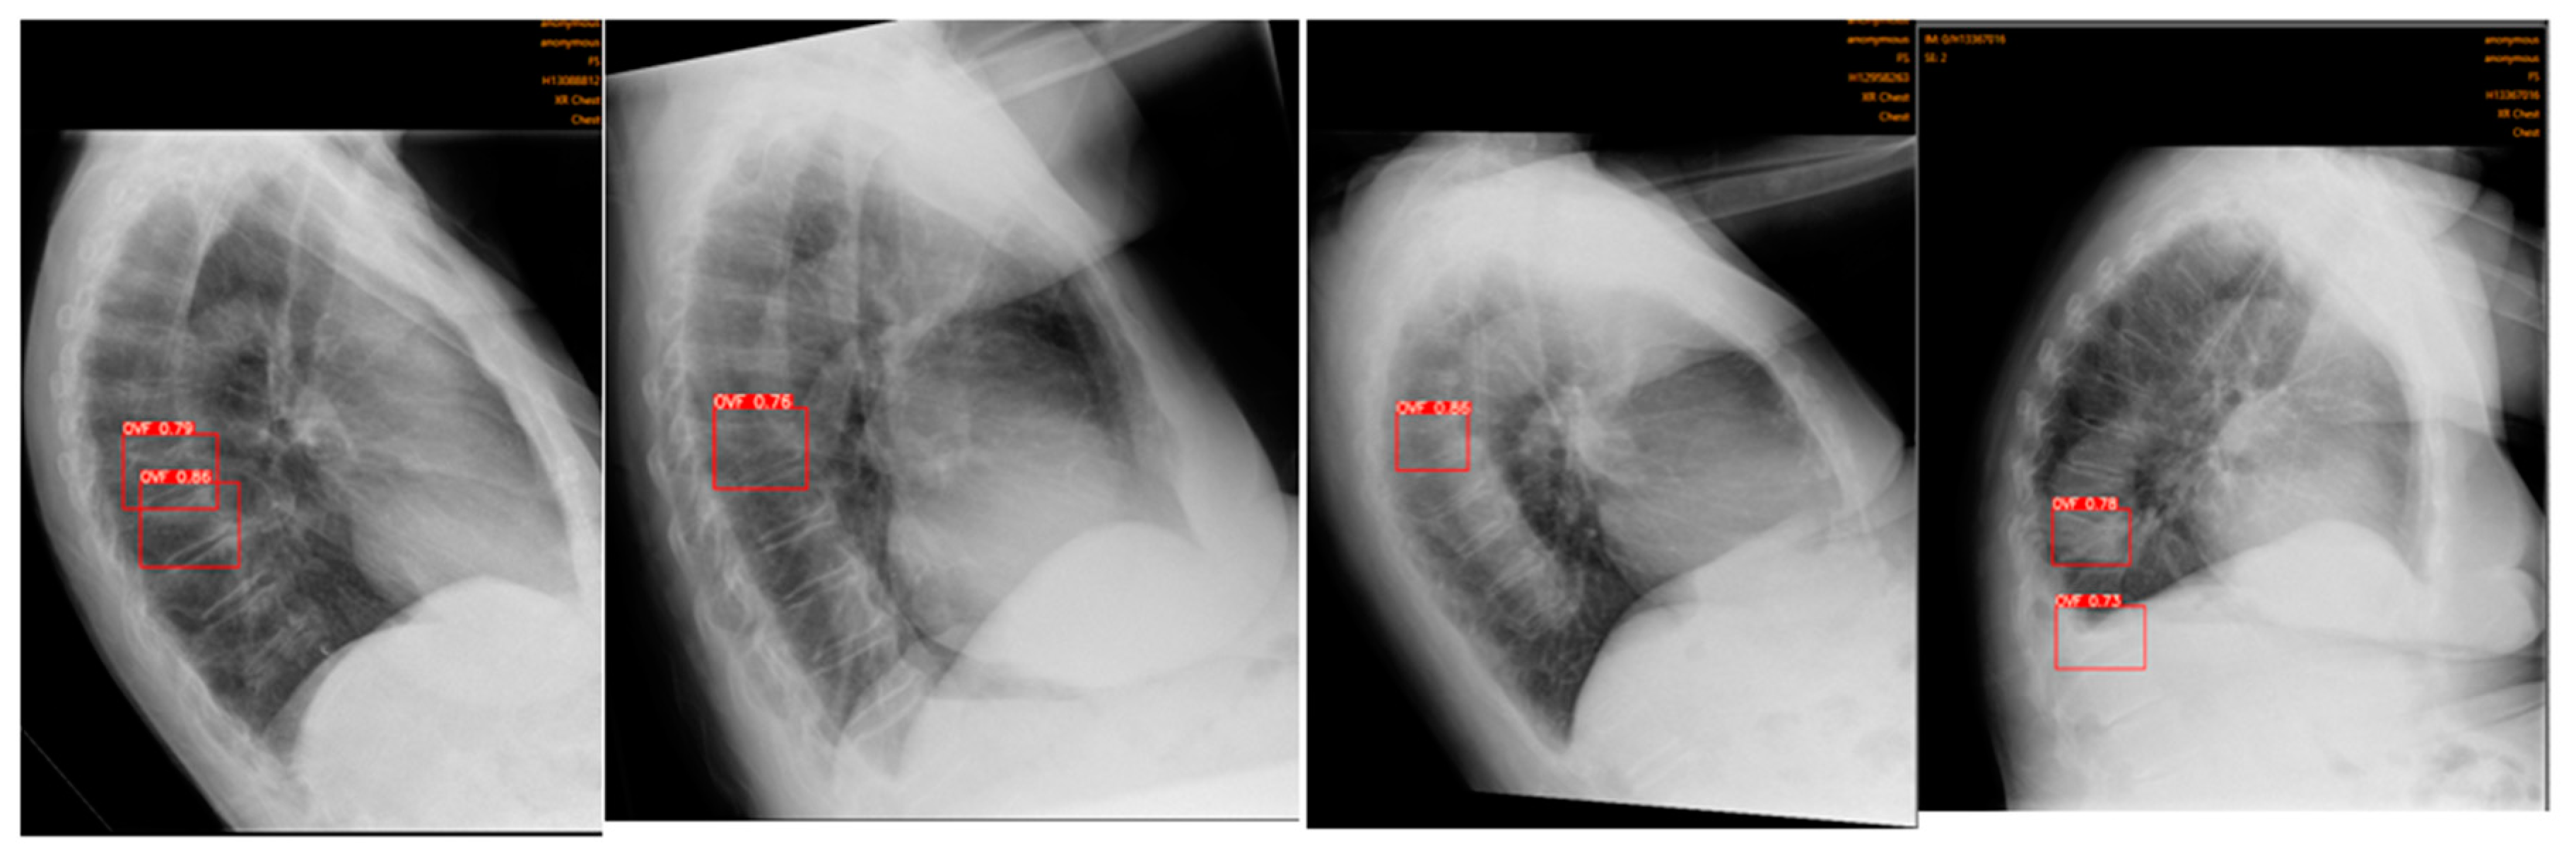

Figure 3. Example of a false negative. OVFs detected by consultant radiologist (gold standard) in red, un-detected by Ofeye1.0. The overall false negative rate was 14.9%.